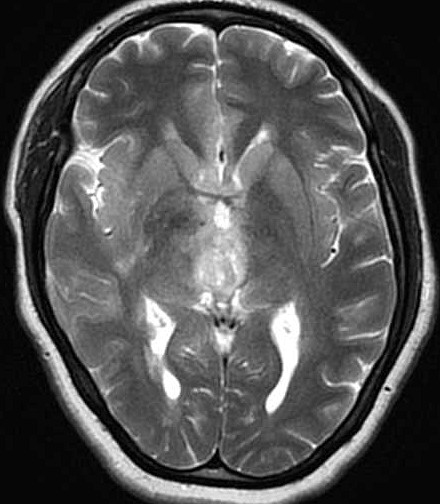

| Fem. 17a. |

| Nódulo sólido homogêneo preenchendo o III ventrículo, com limites precisos, com hipossinal em T1 e hipersinal em T2 e FLAIR, que se impregna por contraste paramagnético. Lesão menor implantada no assoalho do IV ventrículo provavelmente representa disseminação por via liquórica. |

| CORTES AXIAIS, T2 | ||

| F. 17a. Tumor teratóide rabdóide atípico de III ventrículo. RM | HE | VIM, GFAP | HHF35, desmina, 1A4 | AE1AE3, EMA |